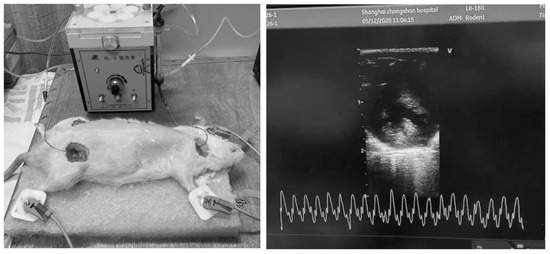

Hemodialysis was conducted over a duration of 2 h, with continuous monitoring under anesthesia and systemic anticoagulation using heparin. Following the treatment, extracorporeal circulation was terminated, and the blood within the circuit was safely reinfused into the rats using an air-driven method (Figure 1).

Figure 1. Hemodialysis and echocardiographic monitoring in rats.